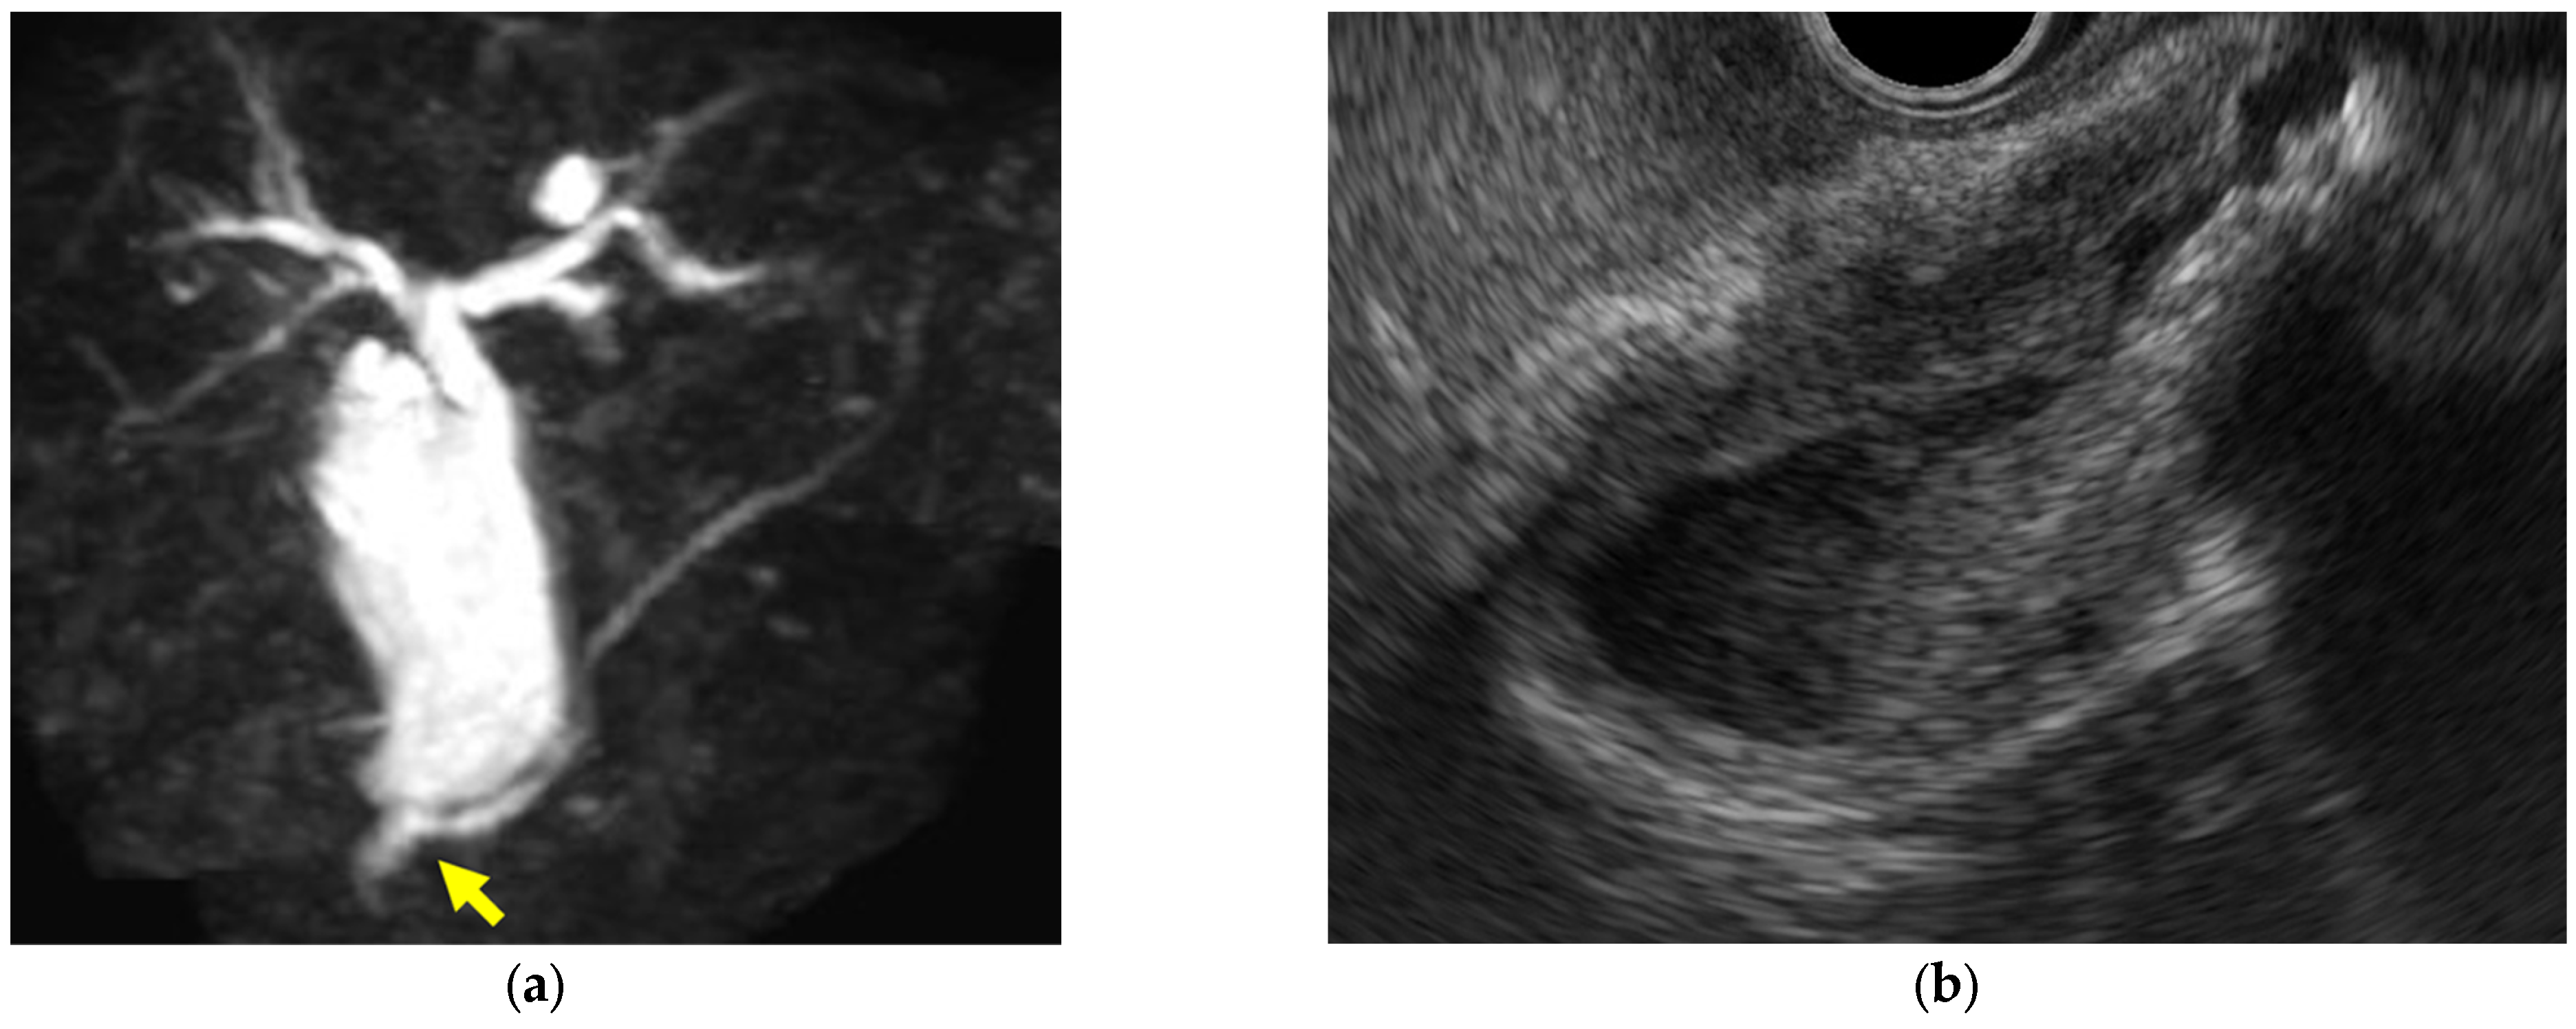

- Immunoglobulin G4-related sclerosing cholecystitis (IgG4-CC) (Figure 3)

- GB mucosal hyperplasia associated with pancreaticobiliary maljunction (PBM) (Figure 4)